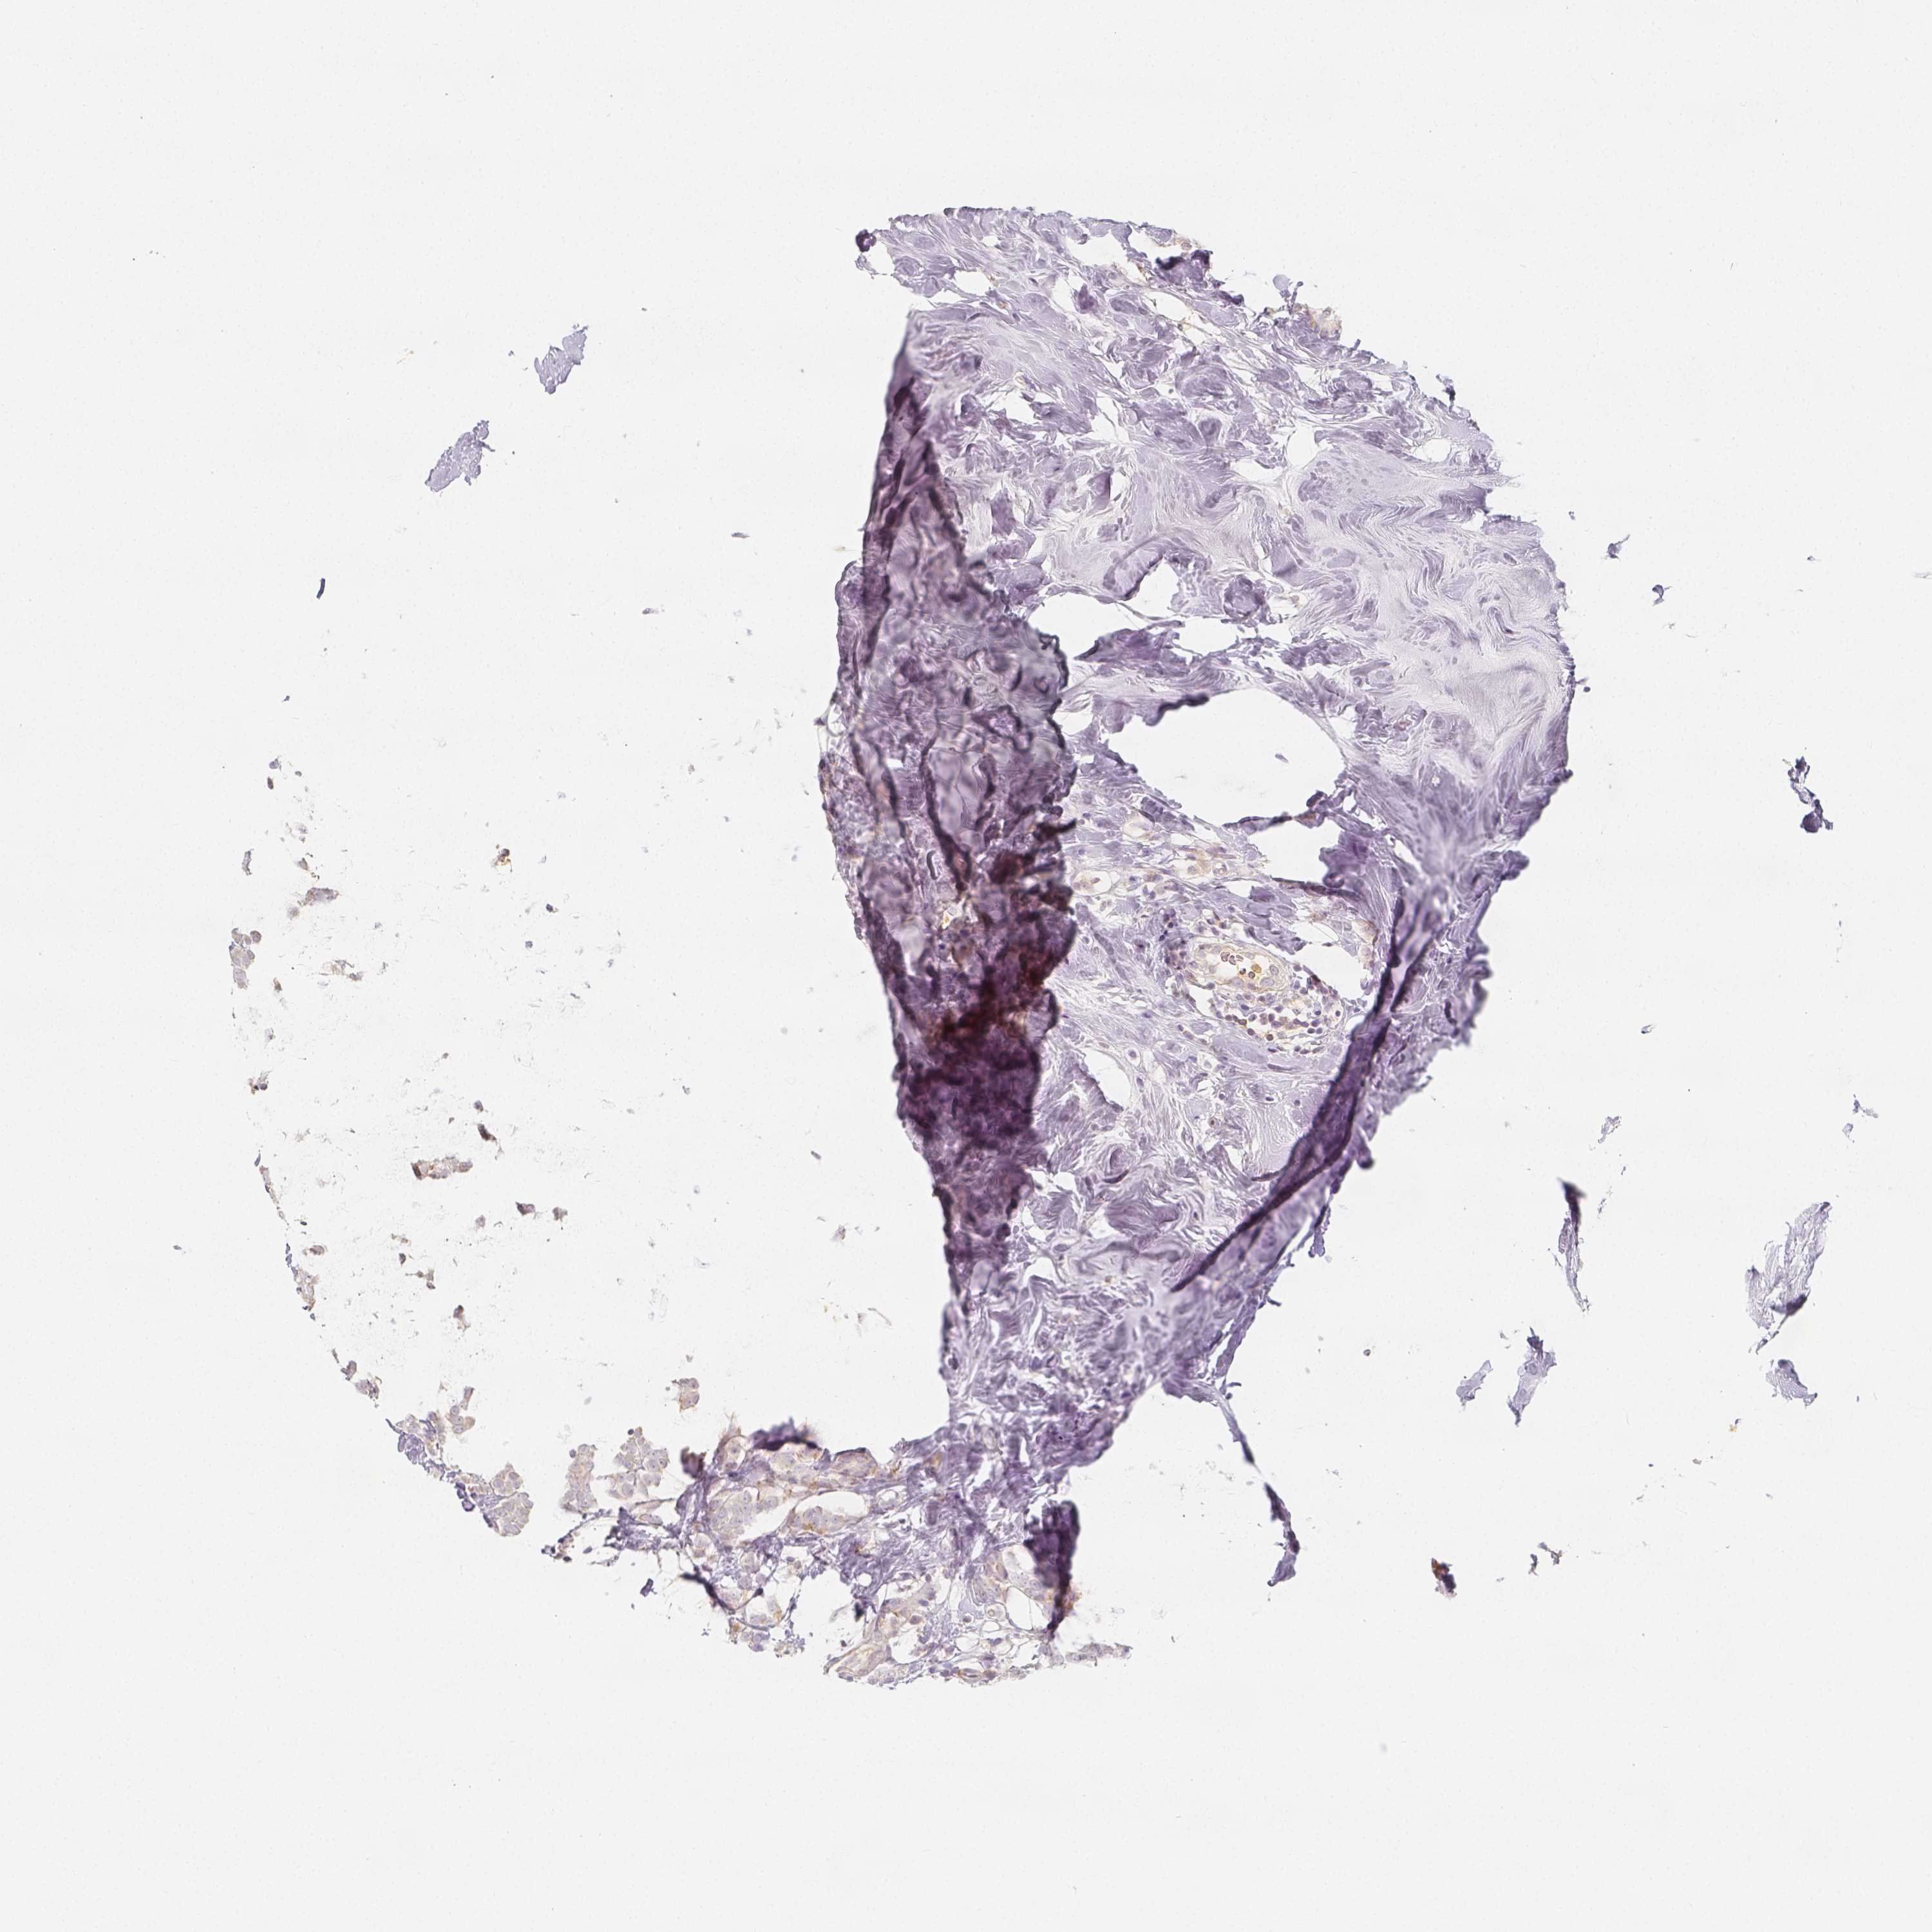

BRCA TCGA BRCA VALIDATION PROTEIN EXPRESSION